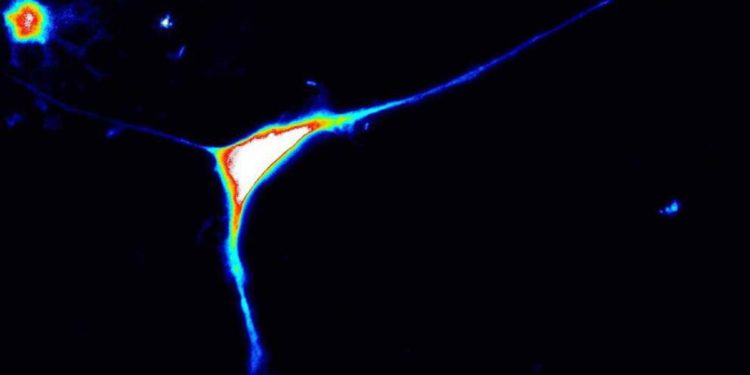

Per approfondire i meccanismi patologici correlati alle mutazioni del gene Caprin1, Lisa Pavinato, dottoranda del Dipartimento di Scienze mediche, ha lavorato per quasi un anno nel laboratorio della Brunhilde Wirth all’Istituto di genetica umana di Colonia. “Abbiamo utilizzato la tecnologia Crispr/Cas9 per modificare cellule pluripotenti umane in coltura in modo da spegnere una delle due copie del gene, mimando così la situazione dei pazienti – spiega Pavinato – La parte più complessa dello studio è stato derivare dei neuroni da queste cellule, e studiarne la funzione in laboratorio”.

La ricerca ha dimostrato che perdere una delle due copie di Caprin1 causa un’alterazione della organizzazione e della funzione dei neuroni, nonché della loro attività elettrica. L’importanza dello studio risiede, inoltre, nella definizione del ruolo biologico di Caprin1 in quanto è stato possibile dimostrare che regola la sintesi di molte proteine nei neuroni regolando l’espressione di molti geni nel cervello. Caprin1 è una proteina molto importante, quindi, uno snodo all’intersezione di numerosi meccanismi biologici dei neuroni, che permetterà di identificare numerosi altri geni associati a disordini del neurosviluppo.